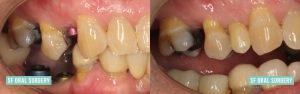

Dental Implants

Patient presented to our office with multiple non-restorable teeth, unfortunately, due to medication-related "dry mouth." His treatment plan included full mouth extractions of his remaining teeth, bone grafting, and same day rehabilitation by placing immediate implants and immediate temporary prostheses, or "bridges." The patient was able to leave our office with a full complement of teeth and was able to eat a "soft diet." Case performed with: Dr. Sukhmani Singh and Dr. Samuel Chiu